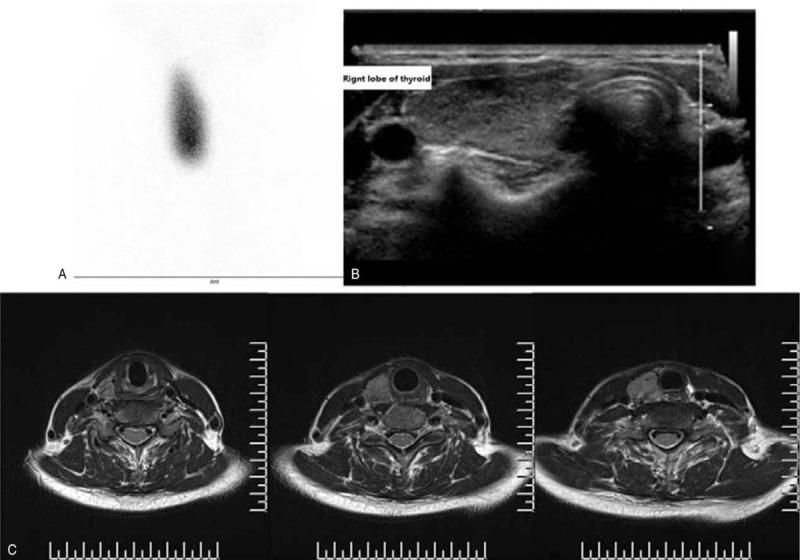

The thyroid function tests were suggestive of thyrotoxicosis. The technetium thyroid scintigraphy only showed an enlarged right lobe with increased tracer uptake. Then, the agenesis of left lobe and isthmus was confirmed by ultrasound and magnetic resonance imaging (MRI). Thus, a diagnosis of GD with hemiageneis of the left lobe and isthmus of thyroid was made.

甲状腺功能检查提示甲状腺毒症。甲状腺锝显像仅显示右叶增大且放射性摄取增加。随后,通过超声和磁共振成像(MRI)证实左叶和峡部缺如。因此,诊断为左叶及甲状腺峡部半侧发育不全的GD。